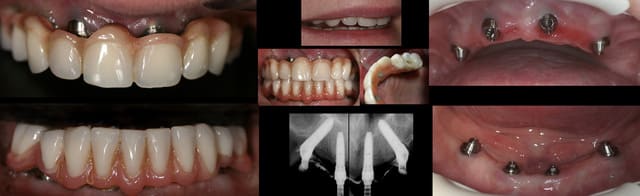

.....1 an et demi après...les 8 fidèles sont toujours là...et voici leur photo de famille.

rem: les 2 PIB ont été réalisé en meme temps...easy et rapide :)

Gigia1anetdemi roumvo - Eugenol

c'est clair que l' esthétique est réalisée en fonction de la ligne du sourire qui doit etre plus basse que la jonction fausse gencive/muqueuse... et les tetes de multiunit doivent pouvoir etre facilement accessible pour le nettoyage.....

aucun pb de phonation à noter.

leger manque de soutien de lèvre inférieure qui sera géré par une injection d' ac hyalu....

ici, nous avons pris l'option dents acryliques.... il y a la possiblité de faire de meme avec des dents en ceram maquillées...les limites sont celles du souhait du patient, du prothé et des sousous...c' est dejà pas donné ;)